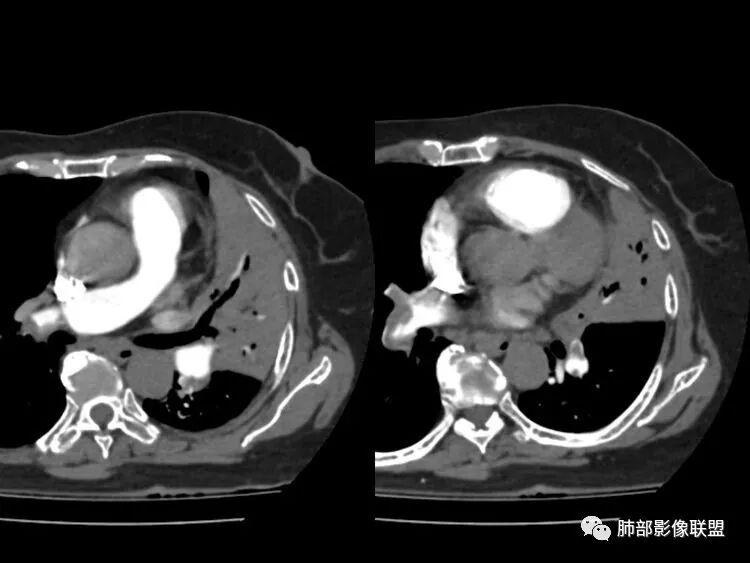

患者近期胸闷气促,D2高,低氧血症,肺动脉干增宽,确实需要警惕肺栓塞,可以做个CTPA排除一下。一元结核不太好解释主诉

南边:这个是左上肺基本没啥功能所致吧肺动脉粗了尘缘:晨读:一、肺栓,CTPA去证实,这个一定有的,二,结核?这个不一定是,也不一定有结果,3、间质性肺水肿,这个应该有,但结果不一定能体现出来。综上:考虑肺栓塞伴间质性肺水肿,结核待排。

影像特点支持结核。气促、左上肺病灶似乎不能解释I型呼吸衰竭加上D—二聚体明显升高、肺动脉干增粗,临床需要想到二元可能:肺结核合并肺栓塞可能,需要完善CTPA明确有没有肺栓塞,因为急性肺栓塞是急危重症。

2.纵隔左移。肺动脉增宽。

D-二聚体升高,肺动脉成像等明确患者肺栓塞的存在!